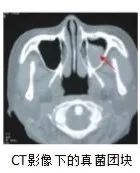

最终在小杨的头颅CT上发现了问题:

小杨的鼻窦腔内有好大一个团块,

几乎把整个鼻窦腔填满了,

鼻窦CT结果提示左侧上颌窦真菌感染。

所以小杨鼻窦腔里的团块

其实是一整团霉菌?!

鼻窦腔内乒乓球大小霉菌团块